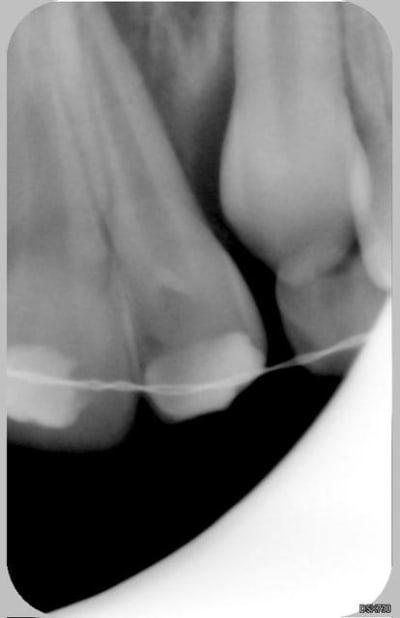

Patiente de 11 ans ayant la 21 expulsée début avril 2006. La dent a été repositionnée en centre de soins. Dans un premier temps, pas de perte de sensibilité. Puis dans un deuxième temps, comme un goût de ça tourne mal avec certainement rhyzalyse interne de la 22 (traitement thermafil pas d'école).

la on est dans un tres beau cas de resorption inflammatoire des 21 et 22

La 22 n'était pas cariée, simplement en rotation (elle l'est encore)avec une anatomie atypique (angle mésio-occlusal très fin).

Le milieu est extémement infecté et la résorbtion de la 21 n'est pas aseptique : donc je ne peux pas attendre.

Ci joint la première radio de ces dents avec attelles centre de soins universitaire